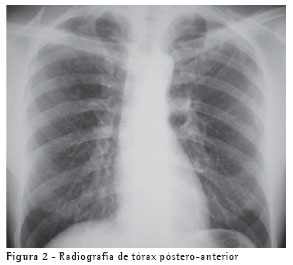

A avaliação radiológica do paciente com DPOC não tem a função de diagnóstico, visto que os achados radiológicos, mesmo nas formas mais avançadas da doença, podem ser inespecíficos. Entretanto, a radiografia de tórax, nas incidências póstero-anterior e perfil esquerdo, é útil para afastar condições associadas.

- Radiografia de tórax de 28/04/02 - Normal (Figura 2);